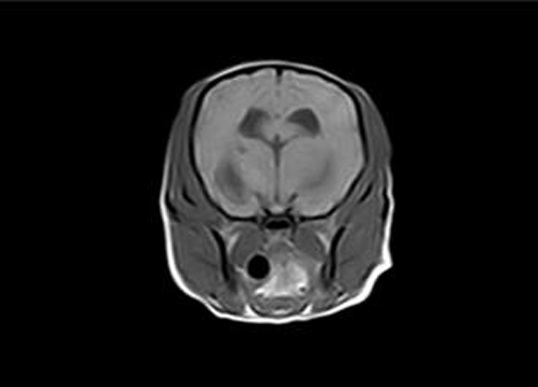

신경내과

신경내과는 동물의 중추신경(뇌,척수)과 말초신경과 관계되는 질환을 진단하고 치료하는 분야입니다. 신경계 질환은 발작, 마비, 운동장애, 치매와 같은 증상을 보일 수 있습니다.

최근 노령 반려동물의 증가로 각종 퇴행성 질환, 신경계 종양으로 인한 신경환자가 많아지고 있습니다. 이에 대한 진단과 치료에 대한 연구가 꾸준히 진행되고 있습니다. 건국대학교 부속 동물병원은 전문적인 진단과 치료를 하고자 최선을 다하고 있습니다.

신경내과 주요 질환

증상 치료 뇌수두증, 육아종성 뇌수막염, 괴사성 뇌수막염, 뇌종양, 중증근무력증, 말초신경병증 등 신경검사, 뇌척수액검사, 뇌파검사, 근전도검사 등